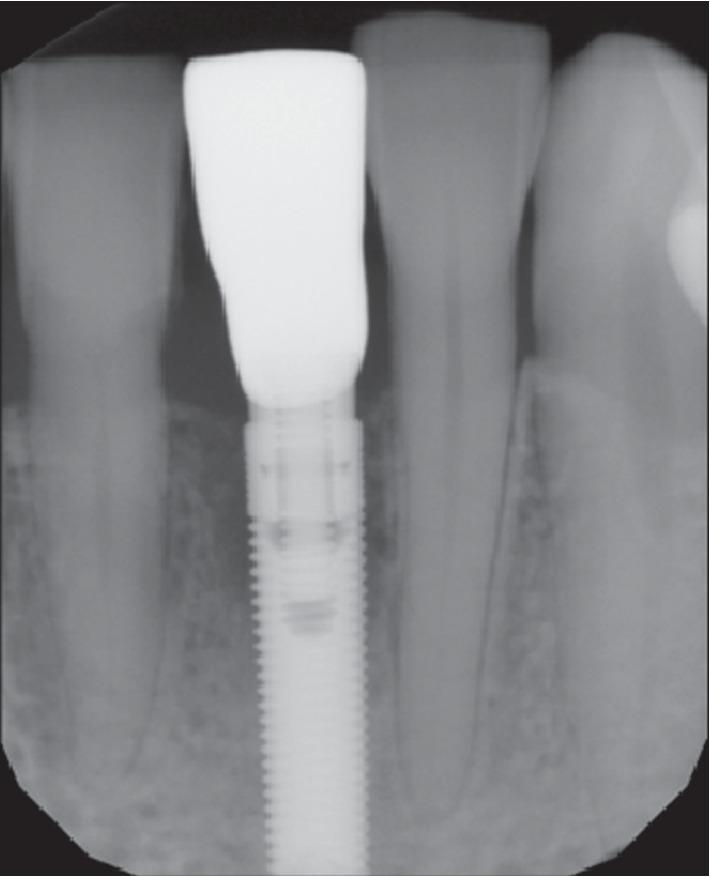

A total of 41 tapered implants were allocated into two groups: the test group ( = 11; 3 males and 8 females; mean age: 62.8 ± 10.7) which received 18 implants as type 1 fresh extraction sockets after teeth removal and the control group ( = 7; 4 males and 3 females; mean age: 65.4 ± 9.7) which received 23 implants placed in healed sockets for a period of at least 3 months. Both the ITV and ISQ data were recorded at the time of insertion ( ). Since ITV (test group) and ITV/ISQ (control group) values were useful for the immediate loading protocol, a screw-retained temporary crown was immediately loaded. ISQ values were recorded after a healing period of 4 months ( ).

总共分配了 41 个锥形种植体,分为两组:实验组(n=11;3 名男性和 8 名女性;平均年龄:62.8±10.7),其中 18 个种植体为拔牙后即刻负载的 1 型新鲜拔牙窝;对照组(n=7;4 名男性和 3 名女性;平均年龄:65.4±9.7),其中 23 个种植体植入愈合时间至少 3 个月的拔牙窝中。在插入时()记录 ITV 和 ISQ 数据。由于 ITV(实验组)和 ITV/ISQ(对照组)值对即刻负载方案有用,因此立即加载螺丝固位临时冠。在愈合期 4 个月后()记录 ISQ 值。